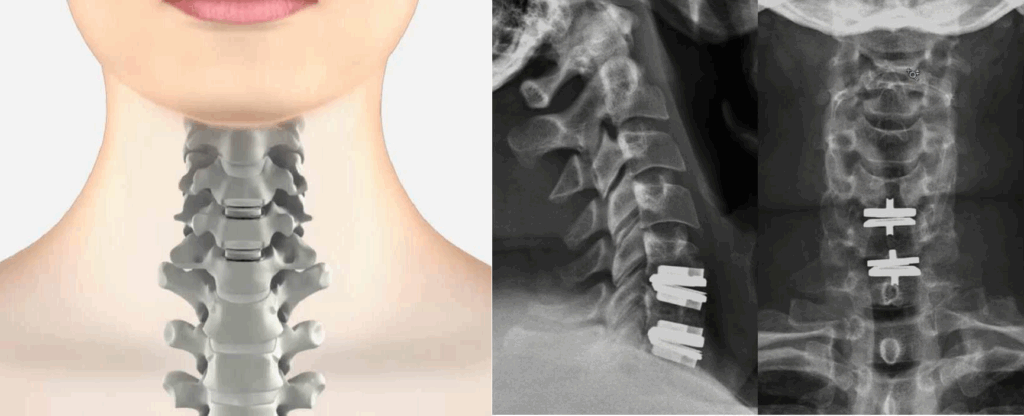

A Discectomia Cervical Anterior com Fusão (ACDF) é o método clássico utilizado por cirurgiões de coluna para tratar hérnias de disco cervicais. Neste procedimento:

- Remoção do Disco Danificado: através de uma pequena incisão na parte frontal do pescoço, o disco comprometido é removido.

- Preparação do Espaço Discal: após a remoção do disco, o espaço criado é preparado para receber um implante.

- Implantação de Enxerto Ósseo ou Cage:

- Enxerto Ósseo (Cirurgia Clássica Original): pode ser utilizado um enxerto ósseo autólogo (do próprio paciente) ou um enxerto ósseo sintético.

- Cage (Espaçador Intersomático): atualmente, é comum o uso de um cage associado a enxerto ósseo sintético. O cage é um dispositivo que mantém a altura do espaço intervertebral e promove a fusão das vértebras adjacentes.

- Fixação com Placa Metálica: uma placa metálica fixada com parafusos pode ser adicionada na frente do enxerto ou do cage para aumentar a estabilidade e possivelmente melhorar a taxa de sucesso da fusão.

O objetivo é que as vértebras adjacentes cresçam juntas e se fundam, eliminando o movimento no segmento afetado e estabilizando a coluna.